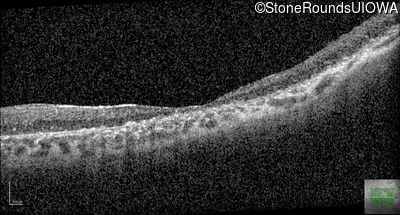

Age at visit: 41 years